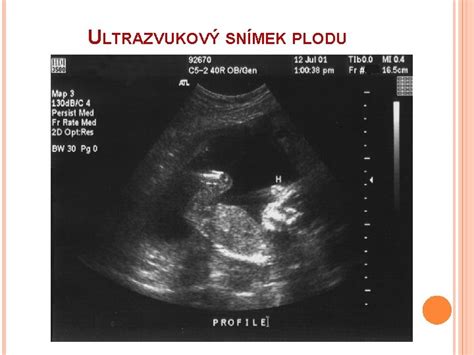

Ultrazvuk využíva vysokofrekvenčné zvukové vlny na vytvorenie obrazu vnútra maternice - bez použitia žiarenia. Je to bezpečný a neinvazívny spôsob, ako sledovať rast a vývoj bábätka počas celého tehotenstva. Pri správnej frekvencii a trvaní je ultrazvuk v tehotenstve bezpečný a medicínsky odôvodnených intervaloch a podľa odporúčaných protokolov by sa mal vykonávať rozumne.

Zatiaľ čo klasický ultrazvuk poskytuje čierno-biely obraz v reálnom čase, 3D ultrazvuk prináša priestorový obraz plodu. Tento pokročilý typ vyšetrenia umožňuje rodičom vidieť realistickejšie tváričku svojho dieťatka, jeho pohyby a gestá. 3D ultrazvuk je obzvlášť vhodný na vytvorenie emocionálneho prepojenia medzi rodičmi a bábätkom. Vykonáva sa na žiadosť rodičov, ideálne v období medzi 26.-30. týždňom tehotenstva.

4D ultrazvuk navyše pridáva do obrazu časovú os, takže môžete vidieť svoje dieťatko v pohybe v reálnom čase, ako keby ste sledovali video.